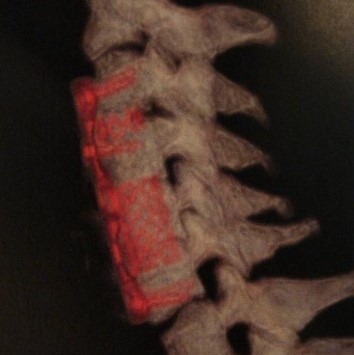

Spinal Cord Tumors

Surgical Treatment